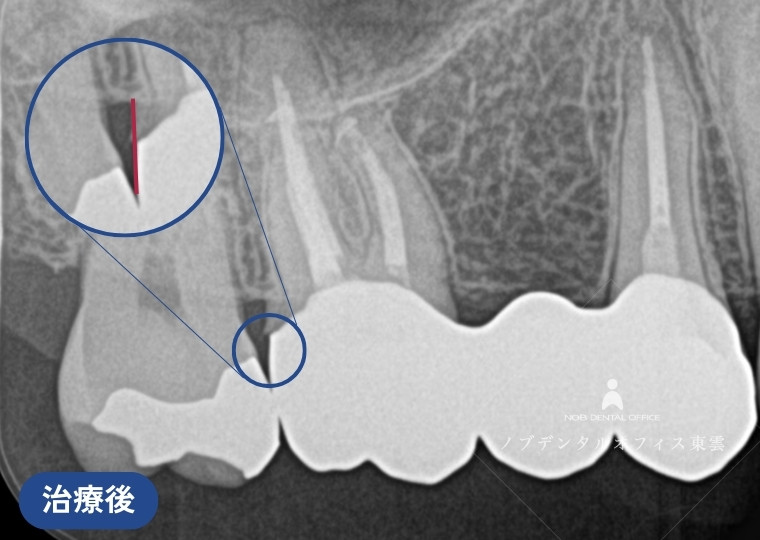

ブリッジの再治療をジルコニアで行った症例(40代女性)

右上の奥歯にすでに保険適用の金属のブリッジが入っていました。

| 治療 | ・根管治療の再治療 ・歯周外科処置(歯ぐきの形態修正) ・ジルコニアブリッジ |

| 費用 | かぶせ物の費用:143,000円×3本 保険適用 |

| リスク | ・経年的に摩耗が起こることがあります。 ・強い噛みしめや歯ぎしりにより、欠けたり外れる可能性があります。 ・歯ぐきの状態によっては境目が見えてくる場合があります。 ・清掃状態や生活習慣によっては境目から虫歯や歯周病が起こることがあります。 |